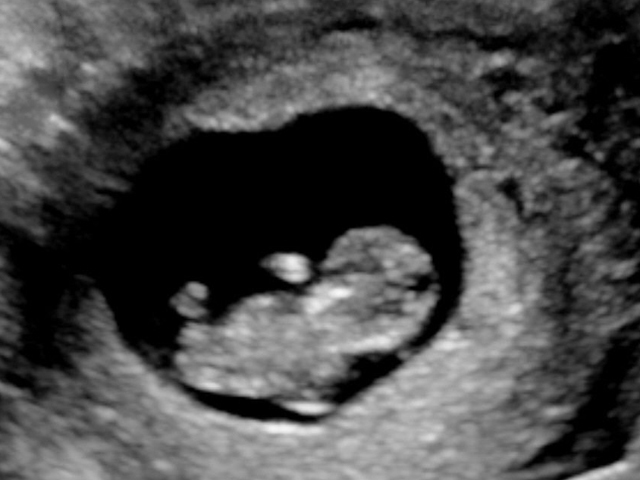

01/12/2017 16:57Bà mẹ từng bỏ thai nhưng kết quả siêu âm sau 15 năm khiến bác sĩ 'rụng rời tay chân'

Gần đây, các bác sĩ ở Ấn Độ đã bị sốc khi tìm thấy bào thai chết lưu suốt 15 năm trong bụng một người phụ nữ 52 tuổi.

Người phụ nữ giấu tên sống tại bang Maharashtra, miền tây Ấn Độ cho biết cô đã từng phải bỏ thai một lần cách đây 15 năm. Vào thời điểm đó, cả bác sĩ sản khoa và bác sĩ phụ khoa của cô đều xác nhận đứa trẻ đã được loại bỏ thành công.

Tuy nhiên, liên tục nhiều năm sau đó, người phụ nữ này thường xuyên bị đau bụng và ba năm gần đây thì nôn mửa liên tục. Cô đã đi khám vài lần nhưng bác sĩ chỉ cho thuốc giảm đau.

Cuối cùng, vì không chịu nổi cơn đau nữa nên cô đã đến tìm tiến sĩ Nilesh Junankar, một chuyên gia sản khoa uy tín tại Ấn Độ.

"Do tình trạng bất thường nên chúng tôi đã tiến hành nội soi và phát hiện ra một sự thật khủng khiếp. Một đứa trẻ 4 tháng tuổi đã "hóa đá" trong bụng người mẹ này.

Kinh nguyệt của bệnh nhân đã ngừng cách đây 5 năm và cô không ở trong độ tuổi sinh sản nên càng khó phát hiện hơn", bác sĩ cho biết.

Ngày 23/11, các bác sĩ đã quyết định phẫu thuật loại bỏ thai đá cho bà mẹ 52 tuổi này. Cuộc phẫu thuật kéo dài 2 giờ đồng hồ. Khi thai được lấy ra, chính các bác sĩ cũng bị sốc vì kích thước của nó.

Thai đá đã gây tắc nghẽn đường ruột và chèn vào ống thực phẩm của cô. Tuy nhiên, tử cung, buồng trứng và ống dẫn trứng vẫn hoàn toàn bình thường.

Mang thai hóa đá có tên khoa học là “lithopedion", là một trong những hiện tượng cực cực kỳ hiếm gặp. Trên thế giới, các bác sĩ ghi nhận có khoảng hơn 300 ca mang thai hóa đá từ trước đến nay và tại Việt Nam cũng có một số trường hợp được phát hiện.

"Tỉ lệ thai lưu hiện nay là khoảng 1/11.000 ca và chỉ có 1,5-1,8% trong số đó phát triển thành thai đá.

Chúng tôi đã loại bỏ thai đá cho người phụ nữ đó. Cô ấy cũng phải loại bỏ khoảng 1,2m ruột đã bị hoại tử do thai chèn vào", bác sĩ phẫu thuật chính cho biết.